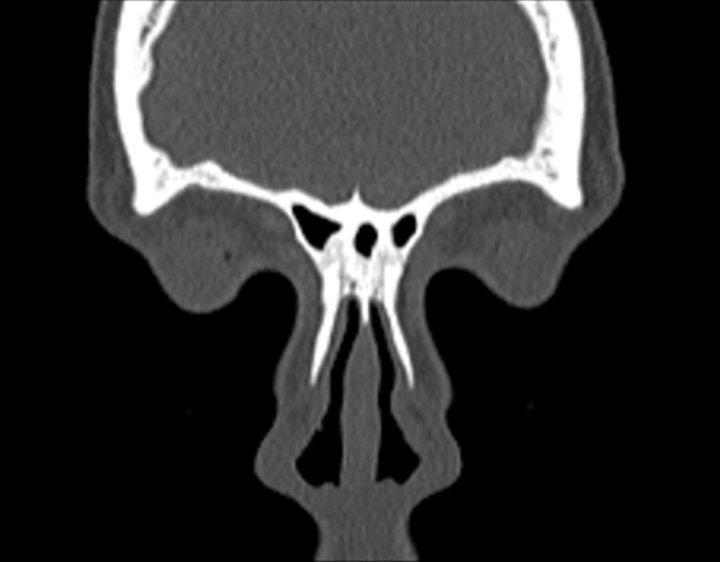

Click any image for labels.